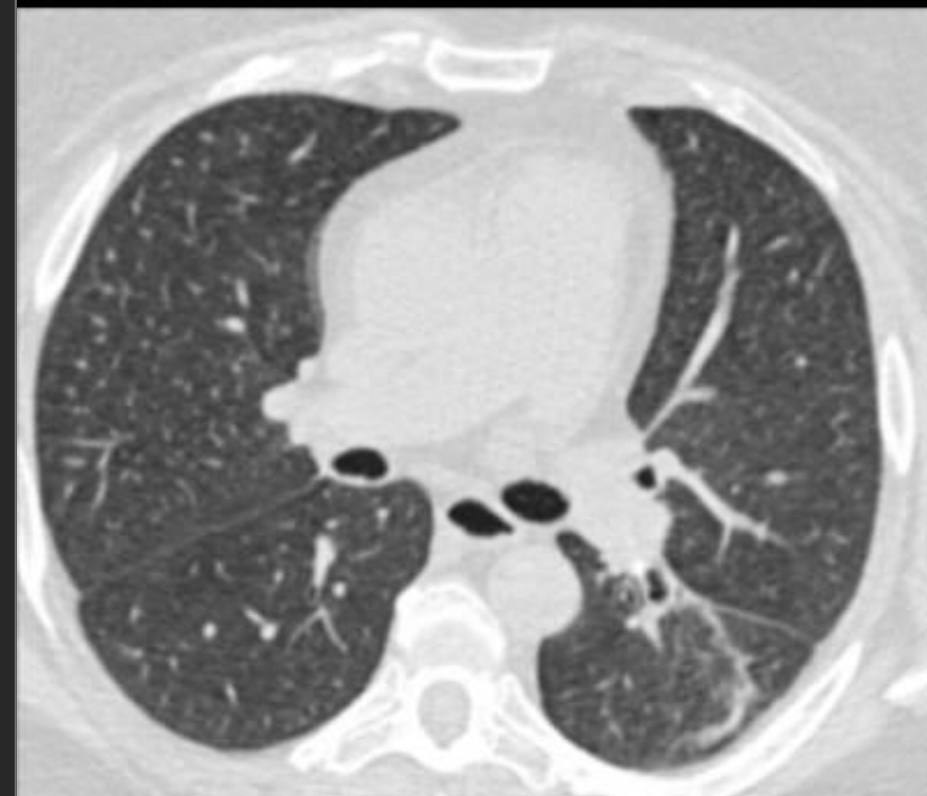

Upper lobe predominant centrilobular ground glass, OR prominent mosaic pattern

Hypersensitivity Pneumonitis

(subacute)

lobular GGO

Need constellation of findings to dx: exposure to an offending antigen, characteristic signs and symptoms, abnormal chest findings on physical examination, and abnormalities on pulmonary function tests and imaging

Mosaic pattern with areas of ground-glass atenuation and areas of low attenuation.